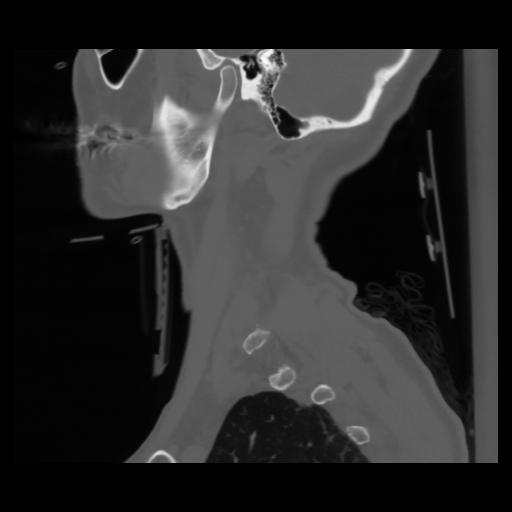

14 P.BLANDAS,,Sagittal,2.000,P.BLANDAS,Sagittal,